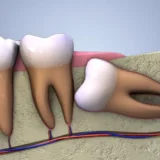

Răng số 6, hay còn gọi là răng cấm, răng hàm lớn, là răng mọc vĩnh viễn đầu tiên và đóng vai trò vô cùng quan trọng